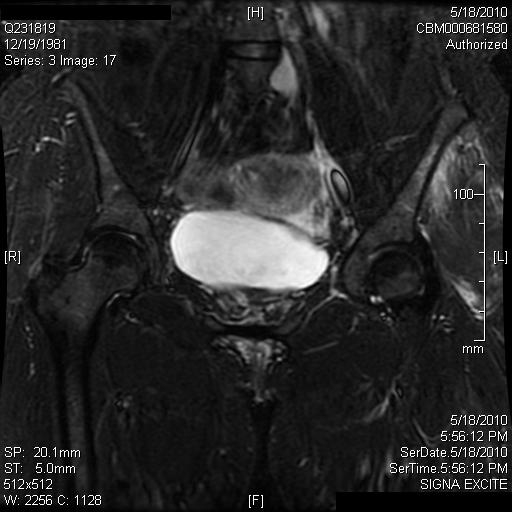

| Female Runner With Bilateral Hip Pain - Page #3 | |||